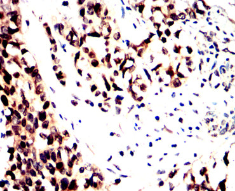

MAP4K1 Mouse Monoclonal antibody[5A10F]

IHC    1/200 - 1/1000